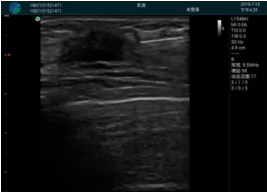

清晰顯示腺體內(nèi)低回聲快影,邊界清晰,包膜較光滑

確定進(jìn)針路徑并實(shí)時(shí)監(jiān)測抽吸針與腫塊位置關(guān)系

抽吸針進(jìn)入腫塊內(nèi)部進(jìn)行旋切

抽吸過程中可見腫塊明顯縮小,并根據(jù)腫塊位置改變針道位置

抽吸旋切后再進(jìn)行超聲復(fù)查,原腫塊區(qū)域未見殘留組織及出血